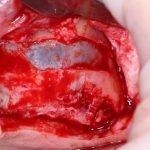

Еще проще. Разрез начинаете от экватора соседних зубов, по такому же принципу, как и в предыдущем пункте. Если адекватный разрез для синуслифтинга мешает сделать коронка зуба или её остатки — спилите их нафиг перед началом работы. Заранее сделанные разрез и скелетирование помогут вам аккуратно удалить зуб. Далее, скелетируетесь примерно на 10 см выше проекции щечных корней и вперед, делать дырку в полость:

Даже если вы делаете операцию над лункой удалённого зуба — здесь вам особенно важно сохранять контроль над дном, ибо длительно существующий периапикальный процесс нередко ведёт к образованию спаек, и риск перфорации очень высок. А иногда бывает и такое, что дно верхнечелюстной пазухи находится ниже апикальных частей лунки. В этом случае можно смело проводить нижнюю границу прямо по лункам — ничего страшного в этом нет, а хороший обзор в таких случаях гораздо важнее.